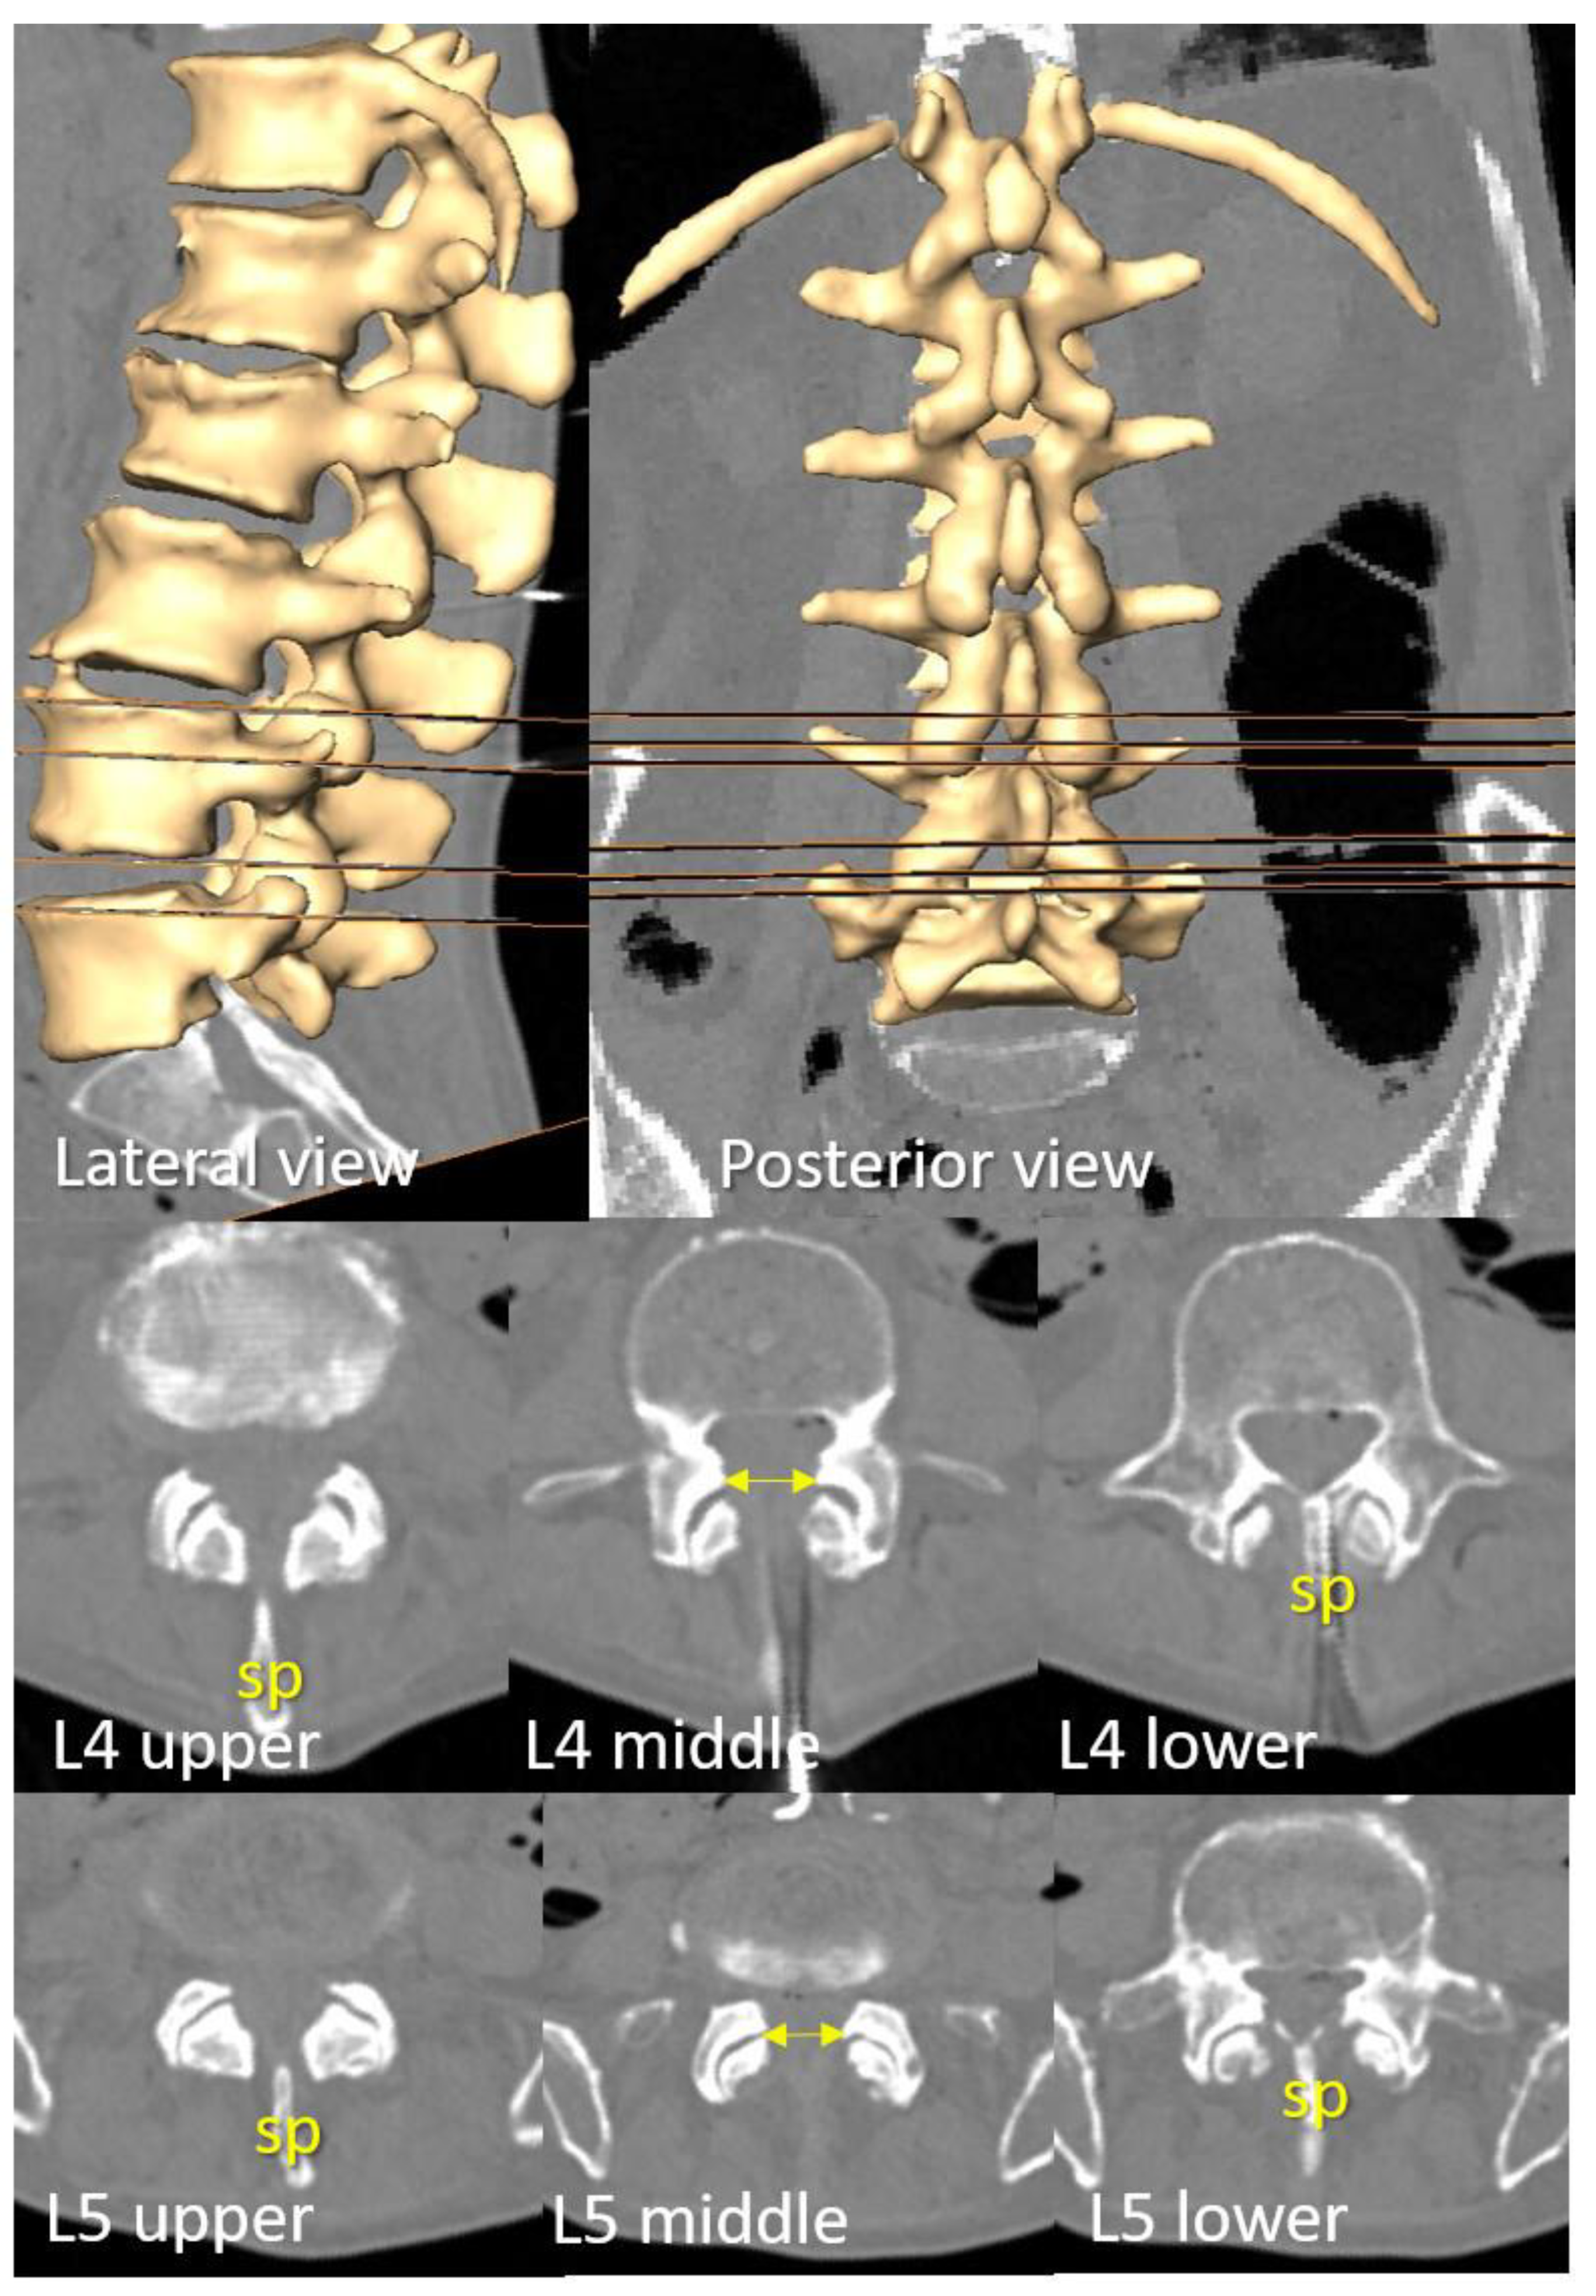

The upper and lower axial planes allowing bilateral and paramedian needle insertion at the commonly used intervertebral levels, L3–L4 and L4–L5, were identified, along with the plane presenting the widest interlaminar window. The distance between the upper and lower axial planes was then measured (

Figure 3).

The upper level of the most medial part of the transverse process correlated with the lower plane where an existing interlaminar window allowed needle insertion perpendicular to the skin. The (tp) of the L5 and L4 vertebrae tends to show a certain cranial inclination. The most lateral part of the (tp) is consistently located slightly caudal to the most cranial plane where a needle insertion remains viable. The ideal plane for needle insertion, characterized by a wider interval between articular processes, is positioned slightly cranial to the lower plane (

Figure 3.

D reconstruction of a representative spine with preserved intervertebral spaces. The upper and lower perpendicular planes to the lumbar skin—where paramedian needle insertion into the dural sac is viable—are displayed in lateral and posterior views of the spine, as well as in axial planes at the L3-L4 and L4-L5 intervertebral levels. Note that the spinous process obstructs median needle insertion at these levels. The level with the widest interlaminar window (indicated by bilateral arrows) is located midway between these planes and coincides with the superior aspect where the (tp) of the L4 and L5 vertebrae become visible, as observable in both axial and coronal views.